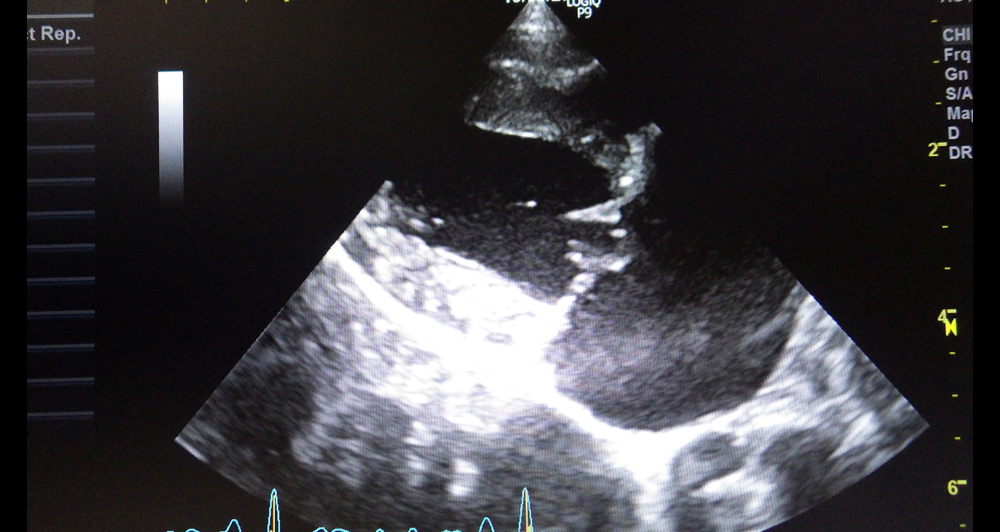

【心臓の構造と働き】

心臓の中では血液は一方通行で流れています。そのために心臓の各部屋の間には弁がついており、その一つが僧帽弁です。

加齢にともない弁やそれを支える腱索が変性し、痛んでくるため、弁がちゃんと閉じなくなってきて起こります。